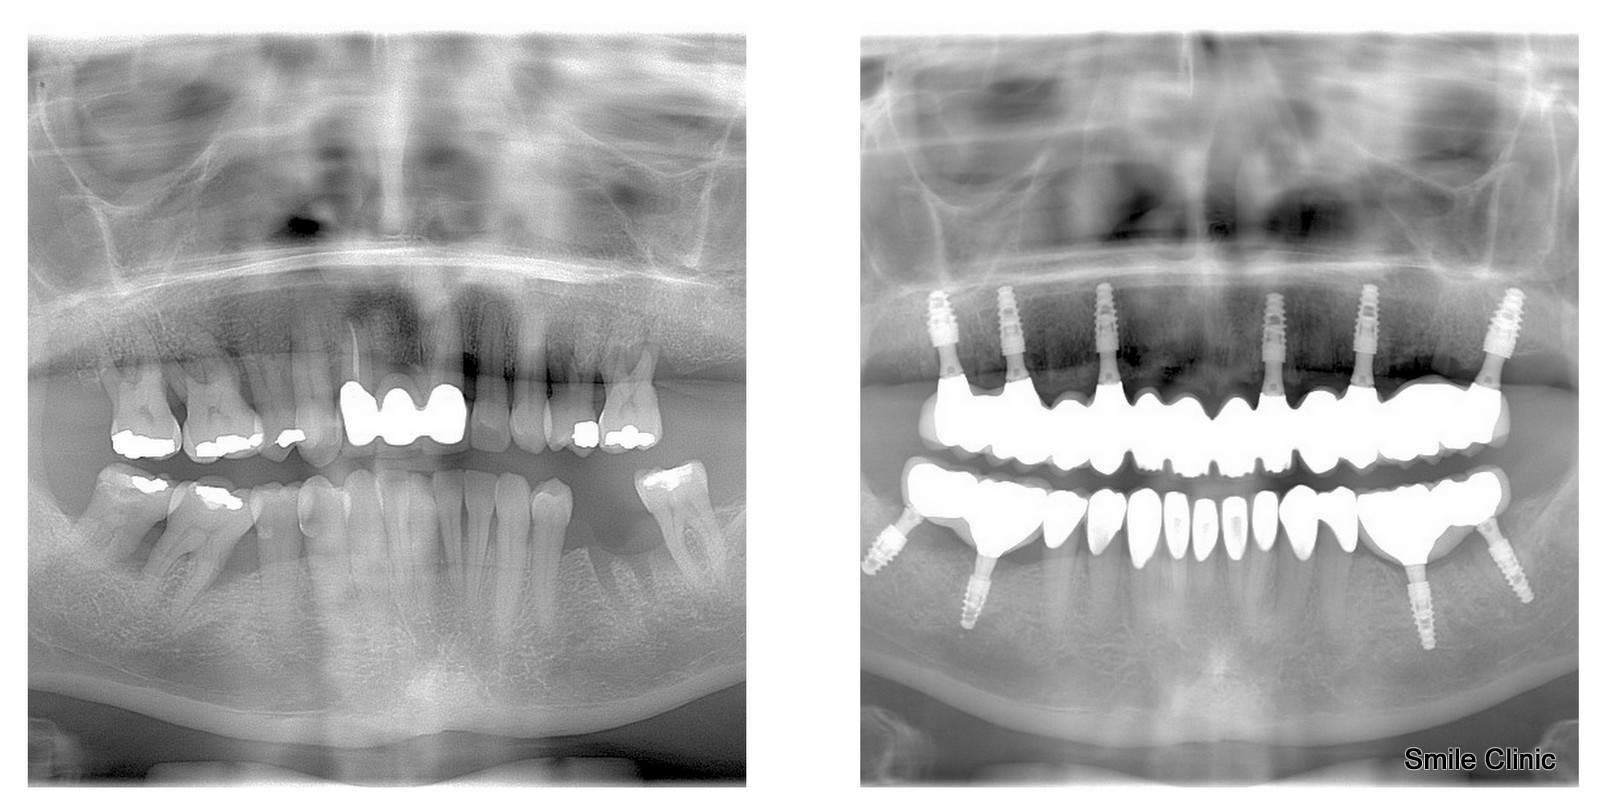

Mrs. Pamela from Manchester, UK, contacted us 2 months after her 50th birthday and her wish was to have all her teeth replaced with dental implants and dental crowns. She made a booking at our dental clinic for a consultation during which we made an X-ray and CT scan for her. Dr. Marek recommended the All on 6 treatment for her upper jaw. He suggested to keep her lower front teeth as they were in a good condition and place only 2 implants to her lower left back side and 2 implants to her lower right back side. After the consultation, Pamela decided to go back to the UK and take some time to make a decision.

We were happy when Pamela contacted us again and booked an implantation session with Dr. Marek in June. Our driver picked her up at the airport and drove her to our dental clinic in Piešťany. Before the doctor could fit the implants he had to extract 13 of her natural teeth. After that, in 5 hours, she already had her dental implants fit in her mouth. The doctor did socket preservation for all of her dental implants to make sure the implants will root to her jaw successfully.

On her final visit, we fit the final implant crowns and also 9 zirconium dental crowns. Pamela left our clinic with a wide smile and she left us this pleasant testimonial: